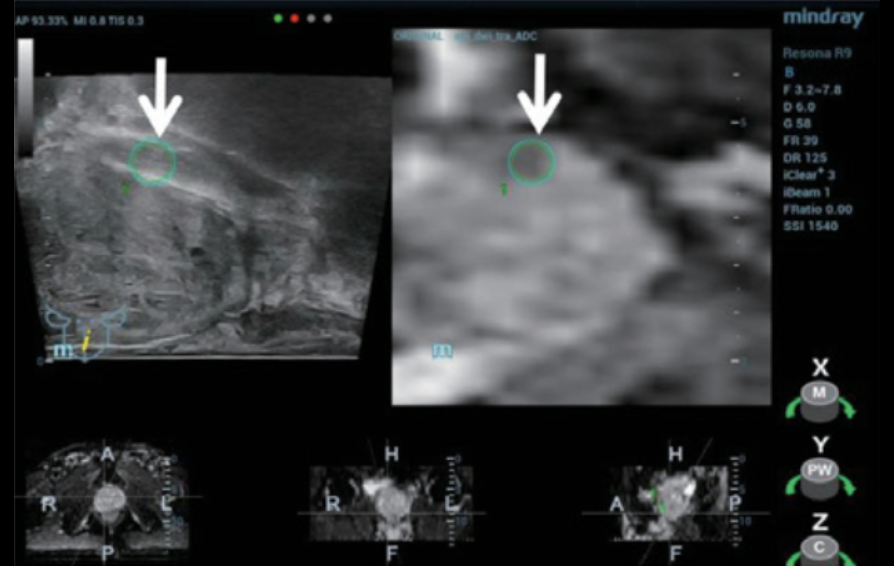

TRUS ?? (figure 1):?

- ??? ??? ???? ??? ??? ???.

- ? ??? ???? ?? ??(heterogeneous) ??? echotexture.

Step 1:???? MRI sequence(Figure 2) ?? ? Resona 9? ??? ??? ??? ??? ??? import ?????.

Step 2:??????? iFusion ?????? ???? TRUS/MRI ???? ?? ? ??(Figure 3) ?? ?? ???(Figure 4).